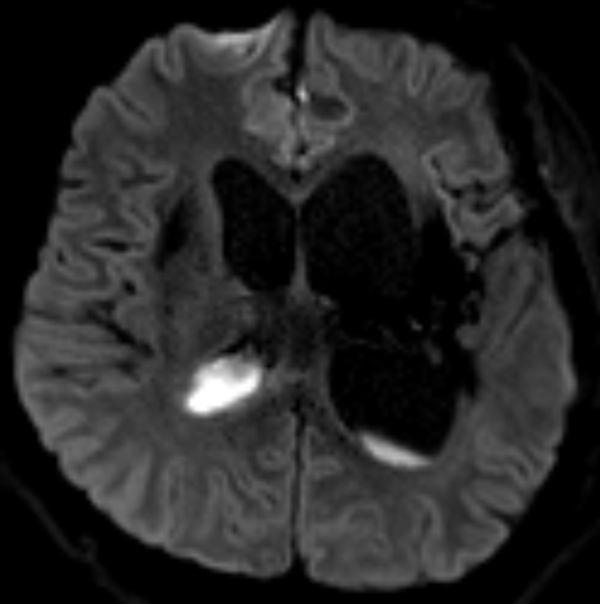

9.MRI에서 나타나는 대표소견 아래와 같이 나타남.

DWI : restricted diffusion (pus)

Hydrocephalus

뇌실염 MRI에서 ependymal enhancement + intraventricular debris 가 특징적, EVD 및 Shunt 삽입력이 있으면 뇌실염 가능성이 훨씬 높음.